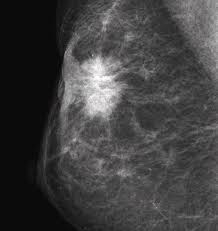

X Ray Mammogram Showing Evidence Of Breast Cancer Stock Image M122 0050 Science Photo Library from media.sciencephoto.com But it's not uncommon that they see something that looks like it might be cancer —a finding that could end up being completely normal, but that needs to be further tested to be sure. What does cancer look like on a mammogram? The tumor cells don't stay within the clear borders of the mass, but instead invade the nearby breast tissue. This type of cancer also changes the appearance of your breasts. This can make it harder for your radiologist to spot signs of breast cancer, since dense tissue and tumors both look white in mammogram images. The look of breast cancer on a mammogram a tumor or lump will appear as a focused white area on the mammogram. A mammogram can show breast changes such as calcifications, masses, or other symptoms that might be cancer. Dr sarah jarvis mbeif a mammogram is abnormal, further tests will be needed.

Invasive breast cancer can appear as a white patch or mass on a mammogram. The tumor cells don't stay within the clear borders of the mass, but instead invade the nearby breast tissue. You may notice dimpling or pitting, and the skin on your breast. A rash isn't the only visual symptom of inflammatory breast cancer. Regular mammograms are the best tests doctors have to find breast cancer early. In a normal breast, a mammogram shows normal skin dark grey fat and lighter grey breast tissue. According to the american cancer society (acs), the most common sign of breast cancer is a new lump or mass in the breast. How can mammograms be used? Cancers may be seen as masses (like a ball, but usually with an irregular shape), areas of asymmetry that resemble normal tissue, calcifications (white specks), and/or areas of architectural distortion (imagine the puckering caused by pulling a thread in a piece of fabric). In this mammogram image, the breast calcifications are in ductal patterns. Healthy mammograms can still vary in appearance. It is important to bear in mind that most women who are asked to come back after. Any area that does not look like normal tissue is a possible cause for concern.

Ibc symptoms are caused by cancer cells blocking lymph vessels in the skin causing the breast to look inflamed. symptoms include breast swelling, purple or red color of the skin, and dimpling or thickening of the skin of the breast so that it may look and feel like an orange peel. What does cancer look like on a mammogram? Cancers may be seen as masses (like a ball, but usually with an irregular shape), areas of asymmetry that resemble normal tissue, calcifications (white specks), and/or areas of architectural distortion (imagine the puckering caused by pulling a thread in a piece of fabric). Tumors may be benign or cancerous. According to the american cancer society (acs), the most common sign of breast cancer is a new lump or mass in the breast. Suspicious findings include clusters of tiny microcalcifications or a density/mass with irregular or spiculated margins. Any area that does not look like normal tissue is a possible cause for concern. This can make it harder for your radiologist to spot signs of breast cancer, since dense tissue and tumors both look white in mammogram images. Breast cancer and some noncancerous (benign) breast conditions can appear white on a mammogram. This is considered an abnormal mammogram, but not necessarily one that's indicative of cancer. Invasive breast cancer can appear as a white patch or mass on a mammogram. By the time it's diagnosed, it usually has grown into the skin of your breast. What does an abnormal mammogram look like?

Ai Assisted Radiologists Can Detect More Breast Cancer With Reduced False Positive Recall Imaging Technology News from www.itnonline.com Breast cancer and some noncancerous (benign) breast conditions can appear white on a mammogram. By the time it's diagnosed, it usually has grown into the skin of your breast. The outer edges of these cells look fuzzy or spiky (called spiculated). They will look carefully at the mammogram to interpret the results. The doctor reading your mammogram will be looking for different types of breast changes, such as small white spots called calcifications, larger abnormal areas called masses, and other suspicious areas that could be signs of cancer. The appearance of normal breast tissue on a mammogram varies from person to person, and no two mammograms look the same. Cancers may be seen as masses (like a ball, but usually with an irregular shape), areas of asymmetry that resemble normal tissue, calcifications (white specks), and/or areas of architectural distortion (imagine the puckering caused by pulling a thread in a piece of fabric). According to the american cancer society (acs), the most common sign of breast cancer is a new lump or mass in the breast.